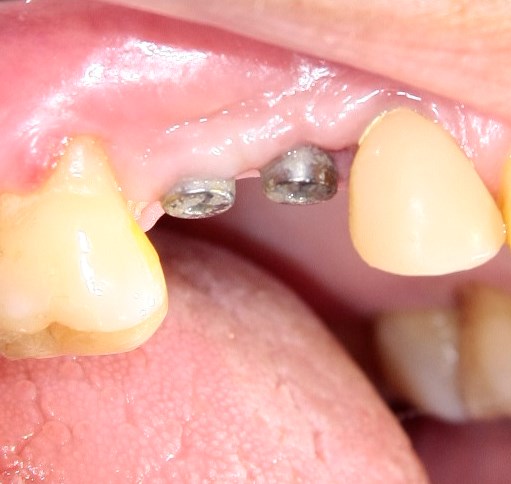

Опыт применения коллагеновой матрицы Mucograft в клинической практике.